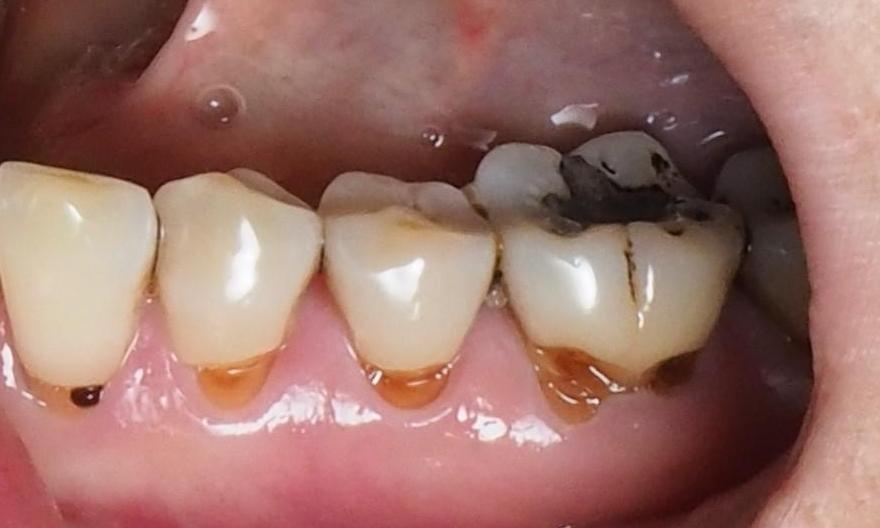

Mrs. J. didn't know anything could be done for the discolored wear areas on her back teeth. After one visit with Dr. Karian, these teeth are reinforced and beautiful again!